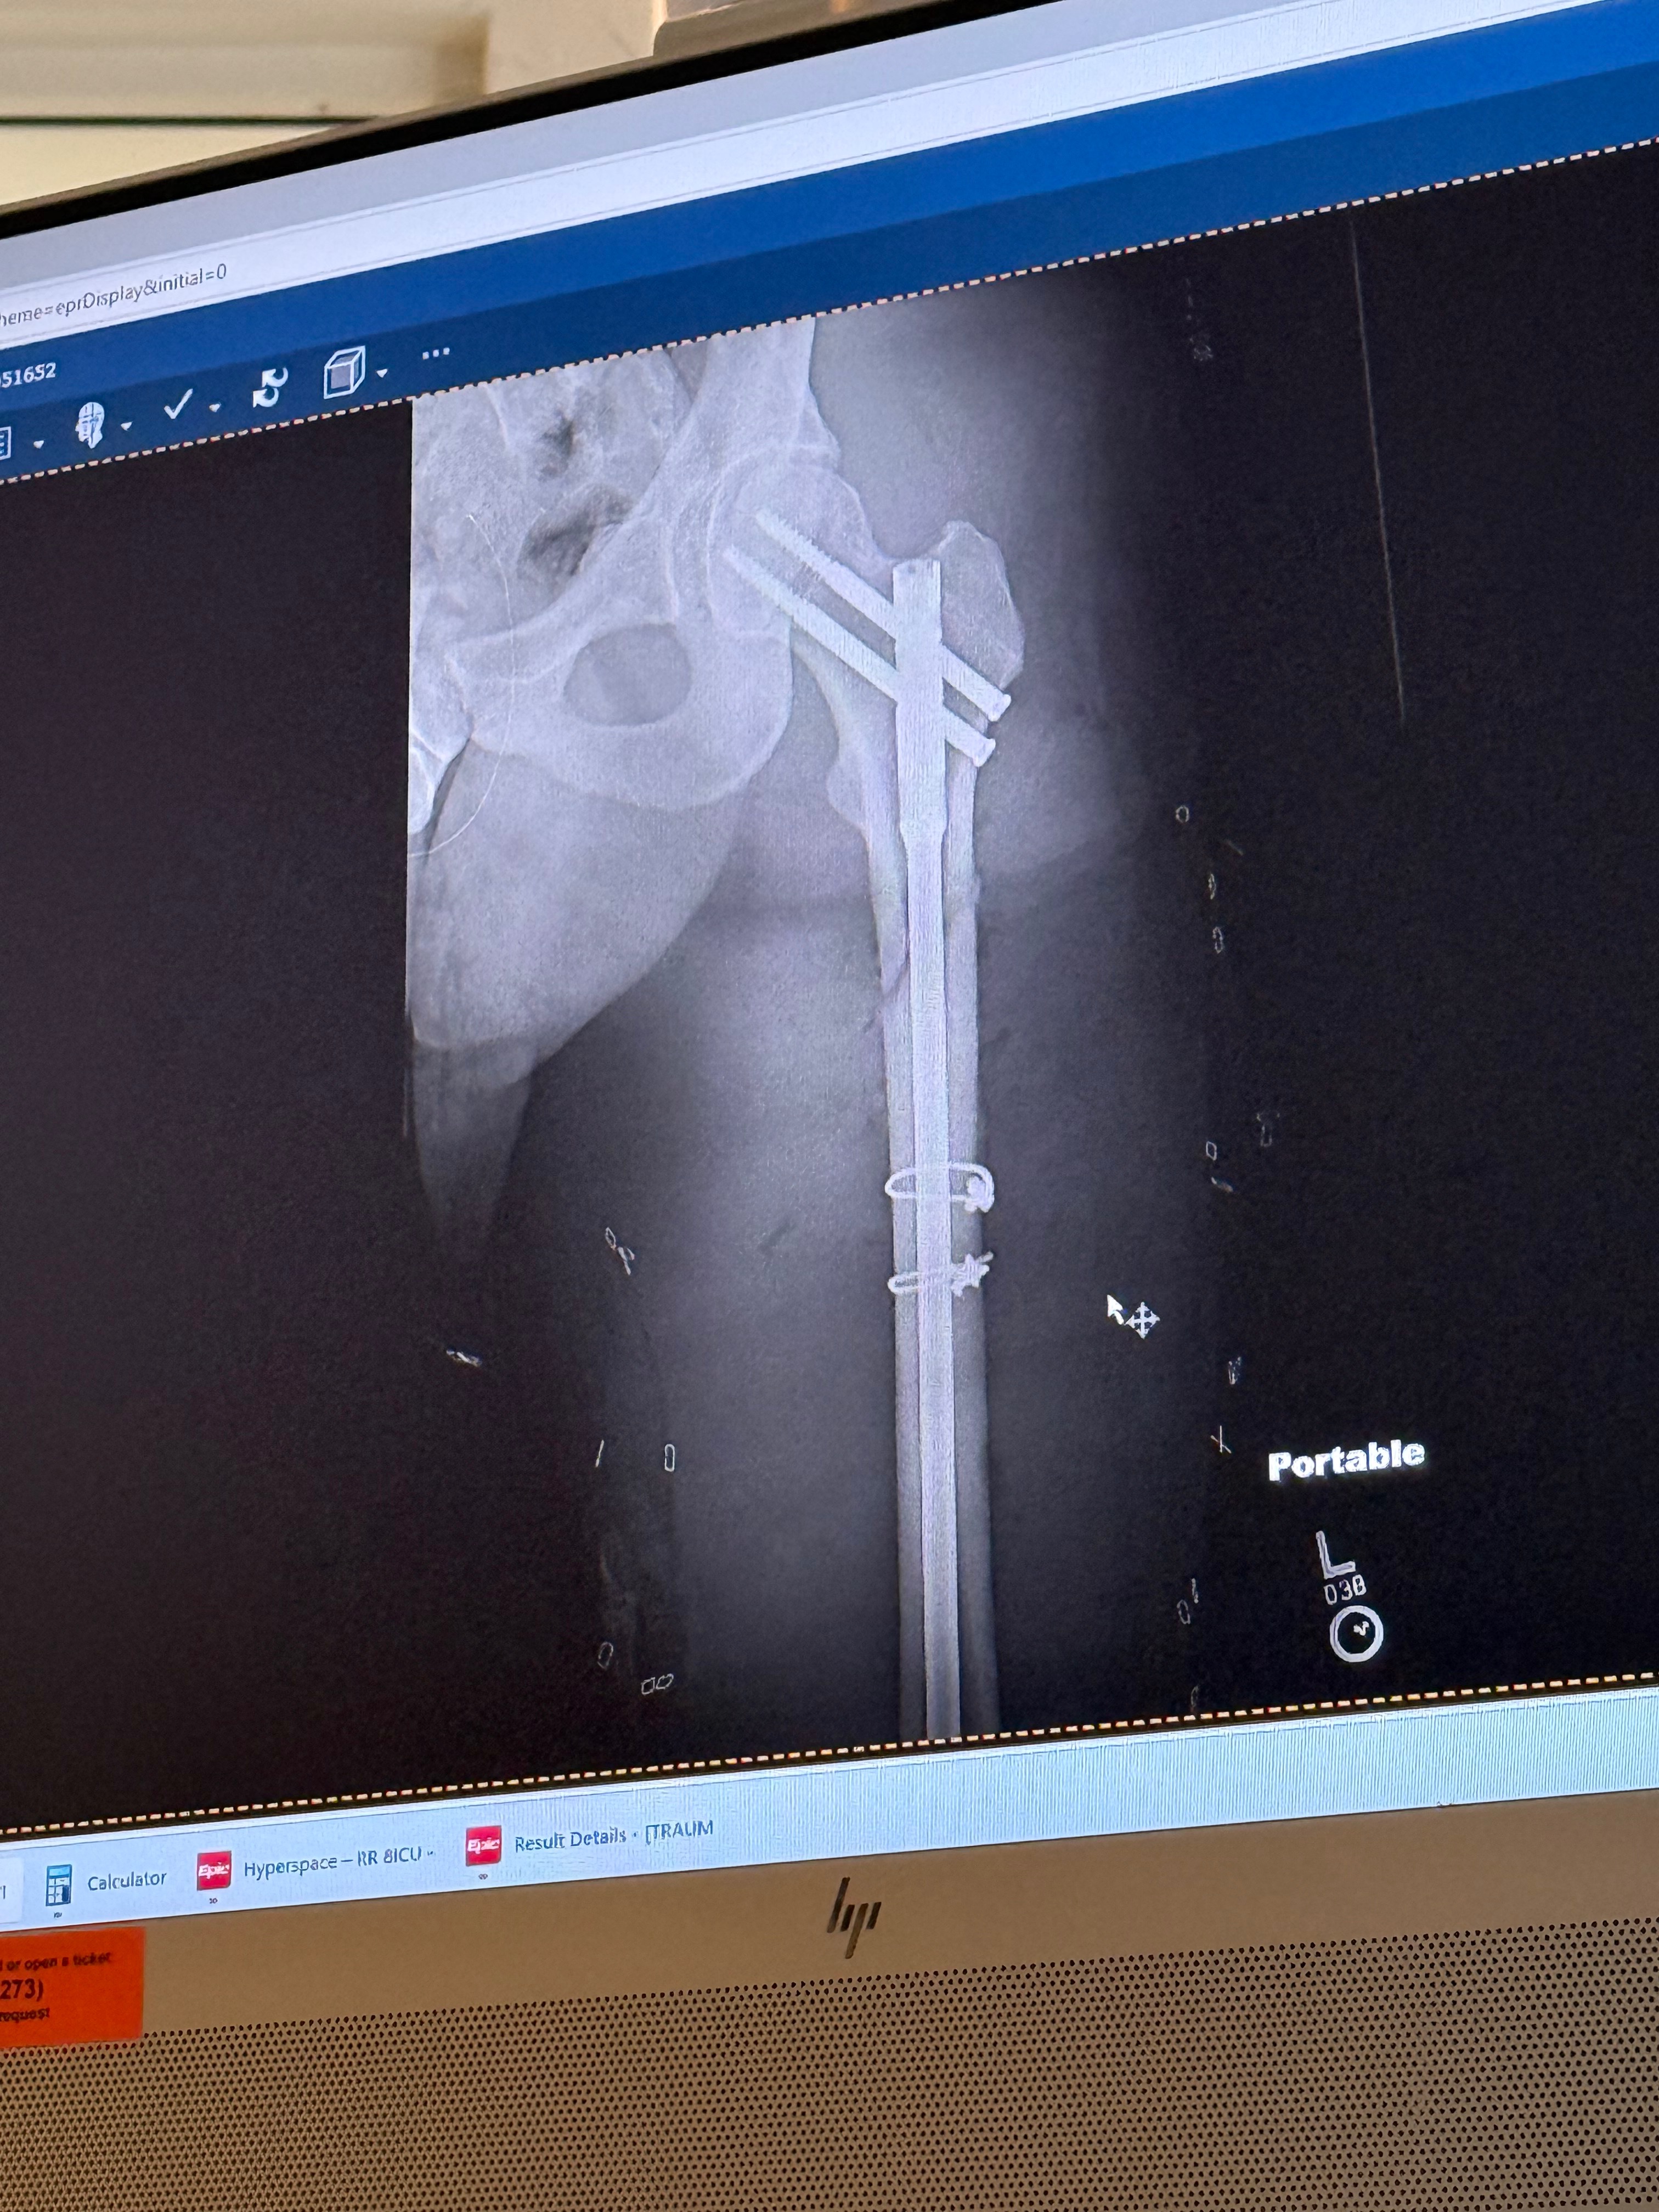

The surgical team moved fast. They repaired the artery, drove a titanium rod through his femur secured with nails and screws, and performed a fasciotomy to relieve the pressure that was building in his leg and threatening to destroy the muscle. That last procedure is the reason he still has full use of his leg. He still has a drain in and a third surgery ahead of him.